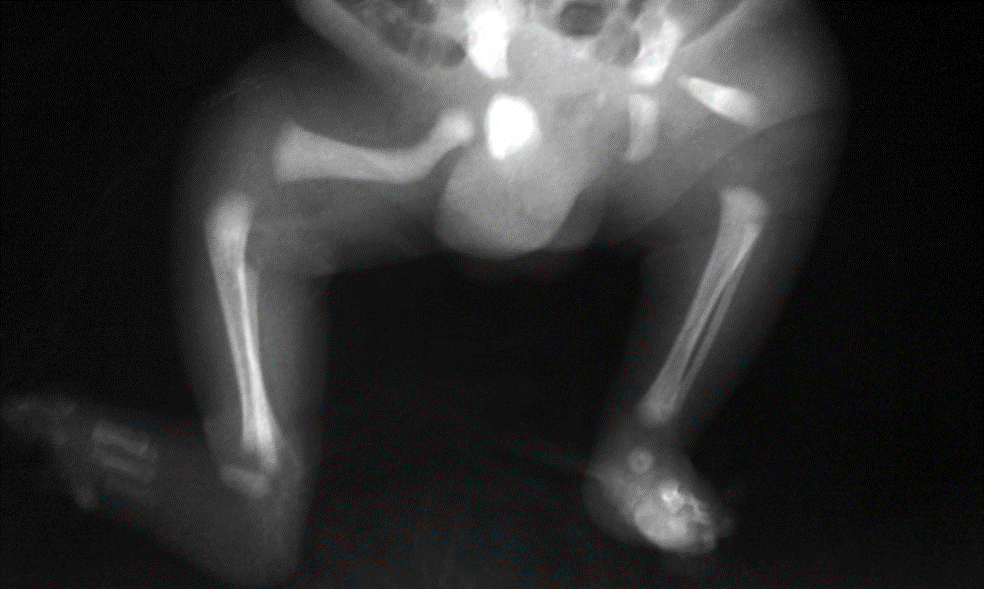

Proximal focal femoral deficiency (PFFD) is radiologically classified into types using the Aitken classification.

Congenital marked hypoplasia of both femurs consistent with bilateral proximal focal femoral deficiency. femoral head and almost all the femur are absent bilaterally, associated with absent acetabula. This is consistent with class D deformity.